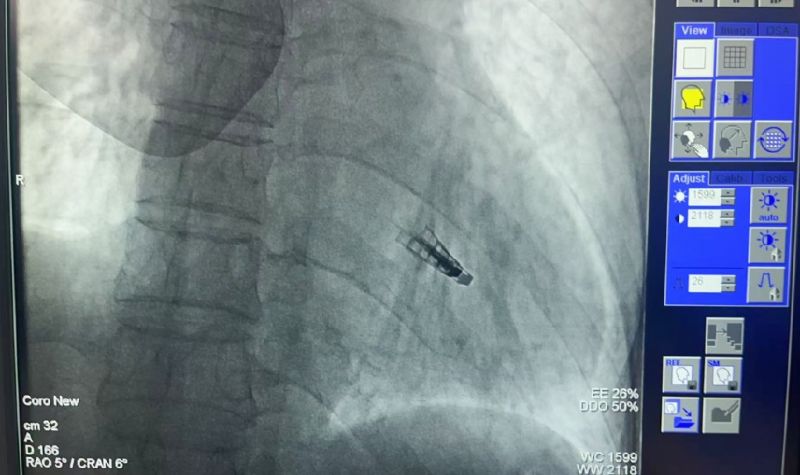

2025年5月9日,延安大学咸阳医院常务副院长兼心血管病院院长吴栋梁介入团队成功为一名73岁“二尖瓣大量返流”患者实施咸阳市首例《经导管二尖瓣缘对缘修复术(TEER)》。

创伤极小:不开胸的“心脏修补术”。仅通过股静脉穿刺,经导管送入夹合器精准修复二尖瓣,避免传统开胸、体外循环等高风险操作。

术前吴栋梁院长、刘雄涛院长、张树远责任总医师再次深入的评估患者整体病情及手术指征,于2025年5月9日下午成功为患者实施了TEER技术,解除了其病痛,术后第一天患者即表示“呼吸顺畅了,整个人都轻松了”。